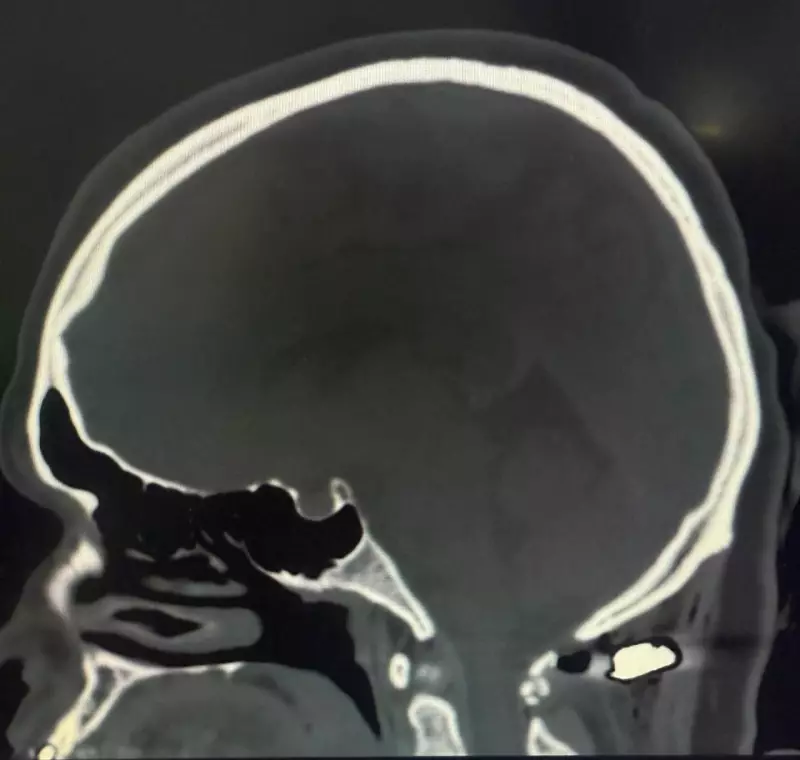

O neurocirurgião responsável pelo caso não escondeu sua surpresa ao analisar as imagens dos exames. "A bala passou a apenas 4 milímetros da medula espinhal", explicou o especialista. "Essa distância mínima fez toda a diferença entre a vida independente e a tetraplegia completa".